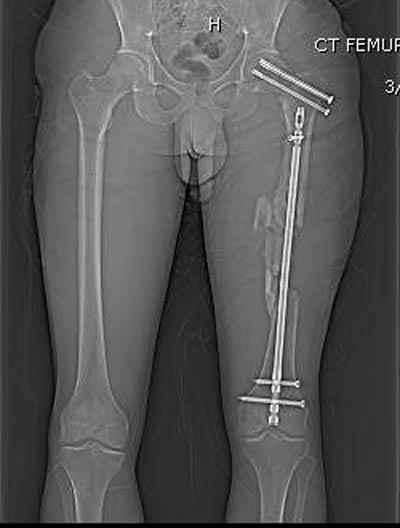

Здесь выставлен ренгенограммы больного, ему 21, травму получил в

результате высокоскоростной погони на украденной машине, которая

закончилась смертью трех остальных“боевых комрадов”. Начатую коллегой

открытую операцию на шейке пришлось закончить мне, установкой винтов и

ретроградной фиксацией бедра. Выписка в обычное сроки и наблюдался

несращения! По истечению 4 месяцев появились признаки варусной

деформации. На СТ срезах несращение шейки и бедра. Риминг, замена на

более толстый гвоздь и вальгусная остеотомия.